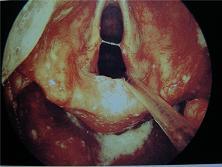

¡á¡á ¿ª·ù¼ºÈĵο°À̶õ? ¿ª·ù¼ºÈĵο°À̶õ À§ÀÇ ³»¿ë¹°ÀÌ °Å²Ù·Î ½Äµµ·Î ³Ñ¾î¿Í Èĵθ¦ ÀÚ±ØÇÏ¿© ¹ß»ýµÈ´Ù. À§ÀÇ ³»¿ë¹° Áß¿¡´Â À§»êÀ̶ó´Â ºñ±³Àû °­ÇÑ »ê¼º¼ÒÈ­¹°ÁúÀÌ ºÐºñµÇ°í À̰ÍÀº À§Á¡¸· ÀÌ¿ÜÀÇ Á¡¸·¿¡´Â »ó´çÈ÷ ÀÚ±ØÀ» °¡ÇØ ½±°Ô¡¦